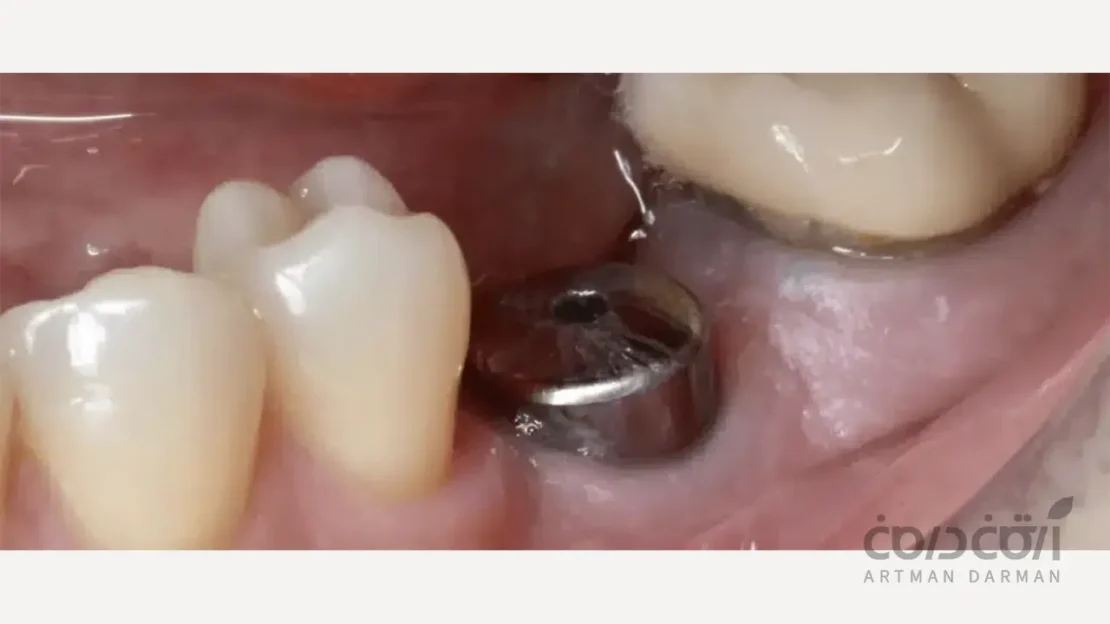

راهکار اول کاشت دو ایمپلنت مجزا به عنوان استاندارد طلایی است

این روش، ایده آل ترین، بیولوژیک ترین و محافظه کارانه ترین راه حل برای جایگزینی دو دندان با ایمپلنت است. در این رویکرد، برای هر دندان از دست رفته، یک ایمپلنت مجزا با روکش مستقل خود کاشته می شود. این روش به دلایل زیر به عنوان استاندارد طلایی شناخته می شود:

بهداشت پذیری بی نقص

وجود دو روکش مجزا به شما اجازه می دهد که به راحتی فضای بین آن ها را مانند دندان های طبیعی با نخ دندان تمیز کنید. سهولت در رعایت بهداشت، برای حفظ سلامت لثه و پیشگیری از بیماری پری ایمپلنتایتیس در بلندمدت حیاتی است.